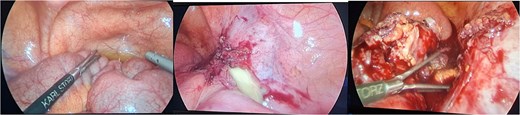

The patient was admitted, and he underwent an emergency laparoscopic appendectomy with partial cecectomy, mesenteric mass excision, and peritoneal lavage. Intra-operative findings included a gangrenous perforated appendix with a right pelvic pus collection, which was aspirated and sent for culture (Fig. 4). A mesenteric mass measuring 6 × 4 cm was noted ⁓70 cm away from the ligament of Treitz distally and excised (Fig. 5). The surgery was completed without complications.

Intra-operative findings, a mesenteric mass measuring 6 × 4 cm was noted ⁓70 cm away from the ligament of Treitz distally.